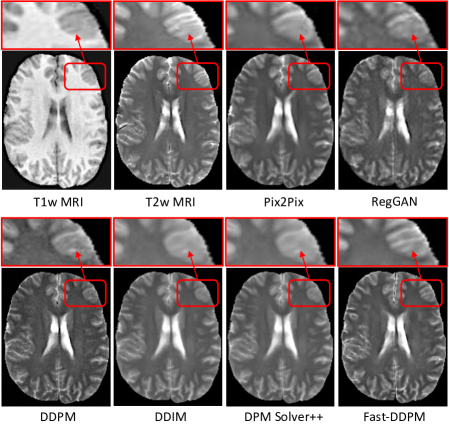

Refer to caption

Figure 6: Qualitative results of the T1w MRI to T2w MRI translation task.

Figure 6 shows the T2w MR images generated by various image-to-image translation methods for a representative subject. Notably, the predictions from Pix2Pix and RegGAN appear blurry and fail to reconstruct the intricate brain structures highlighted by the arrows. DDIM and DPM-Solver++ also produce blurry predictions and struggle to recover fine details effectively. Although DDPM restores some structural details, the reconstructed T2w MRI exhibits a relatively low signal-to-noise ratio. In contrast, Fast-DDPM produces high-quality translations with the sharpest structural fidelity and minimal noise, demonstrating its superior performance.